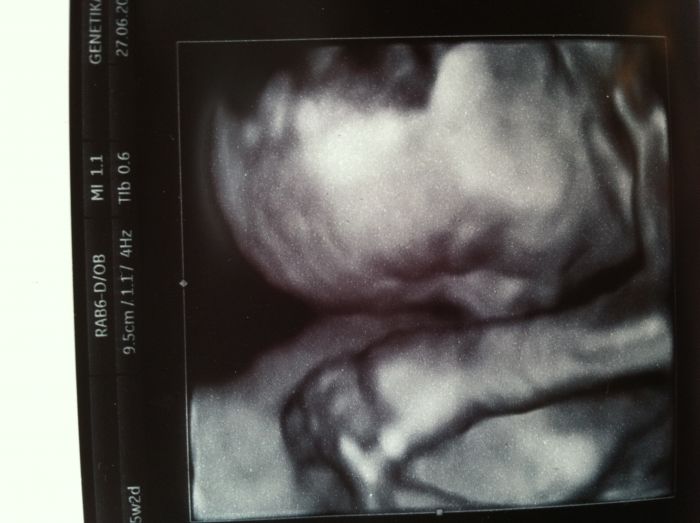

Ja si myslím, ze kdyz se mimi poradne oblečeni, muze ven hned od zacatku, hlavne se vyhýbat uzavřeným prostorům, ale venku to nevadi. jen s tím oblekanim je to trosku alchymie :-) ale ja prosazovala pravidlo raději více nez méně, to hrozily nanejvýš potnicky :-) Nejaka z holcin se ptala na jméno, jestli Nela nebo Sofie, za me určitě Nela ;-) Sofie je krasne jméno, ale je jejich ted strašně moc, ve školce máme samou Sofinku a samého Filipka, takže za me Nela, jednoduche, krasne, lehce zdrobnelinkovatelne :-) Za to my s tema jmenama jsme na štíru :-( Krystufek chce Vincenta a nehne se od nej... Další alternativa je Erik, ale nepřijde vám to takove spis pro obcany pobirajici soc. dávky ve velkém? Muj Ondrašek je v pozadí, no... Líbí se mi ještě Šimon, ale toho blízka kamarádka, malýmu se líbí ještě Jonáš ( to se mi zda byt divny) a Štěpán, 2 kamarádky maji Stepany, takže to asi taky ne, ach jo, asi počkám, az se narodí a pak se rozhodnu :-) Jinak jsme byli včera na 3 D , malej se porad schovával, ale jsme ok, všechny orgány velikostne o funkčně ok, jedna fotka se podařila, video jsme ani nechtěli, kdyz nebylo nic vidět, tak jsme za trictrvtehodinove snažení dali nakonec 100 Kč, což celkem jde, ale musím říct, ze jsem porovnávala tu fotku s Krystufkovo fotkou, hned po narozeni, no a jsou úplne stejni, takže cela ja :-) doufám, ze bude mit aspon barvu vlásku a ocicek po Ladovi :-) Krystufek ma černé oči a hnede vlasy po me, přítel ma špinavý blond a modre oči, tak snad aspon něco z toho převezme :-) přála bych mu to moc :-) zkusím přiložit fotku...